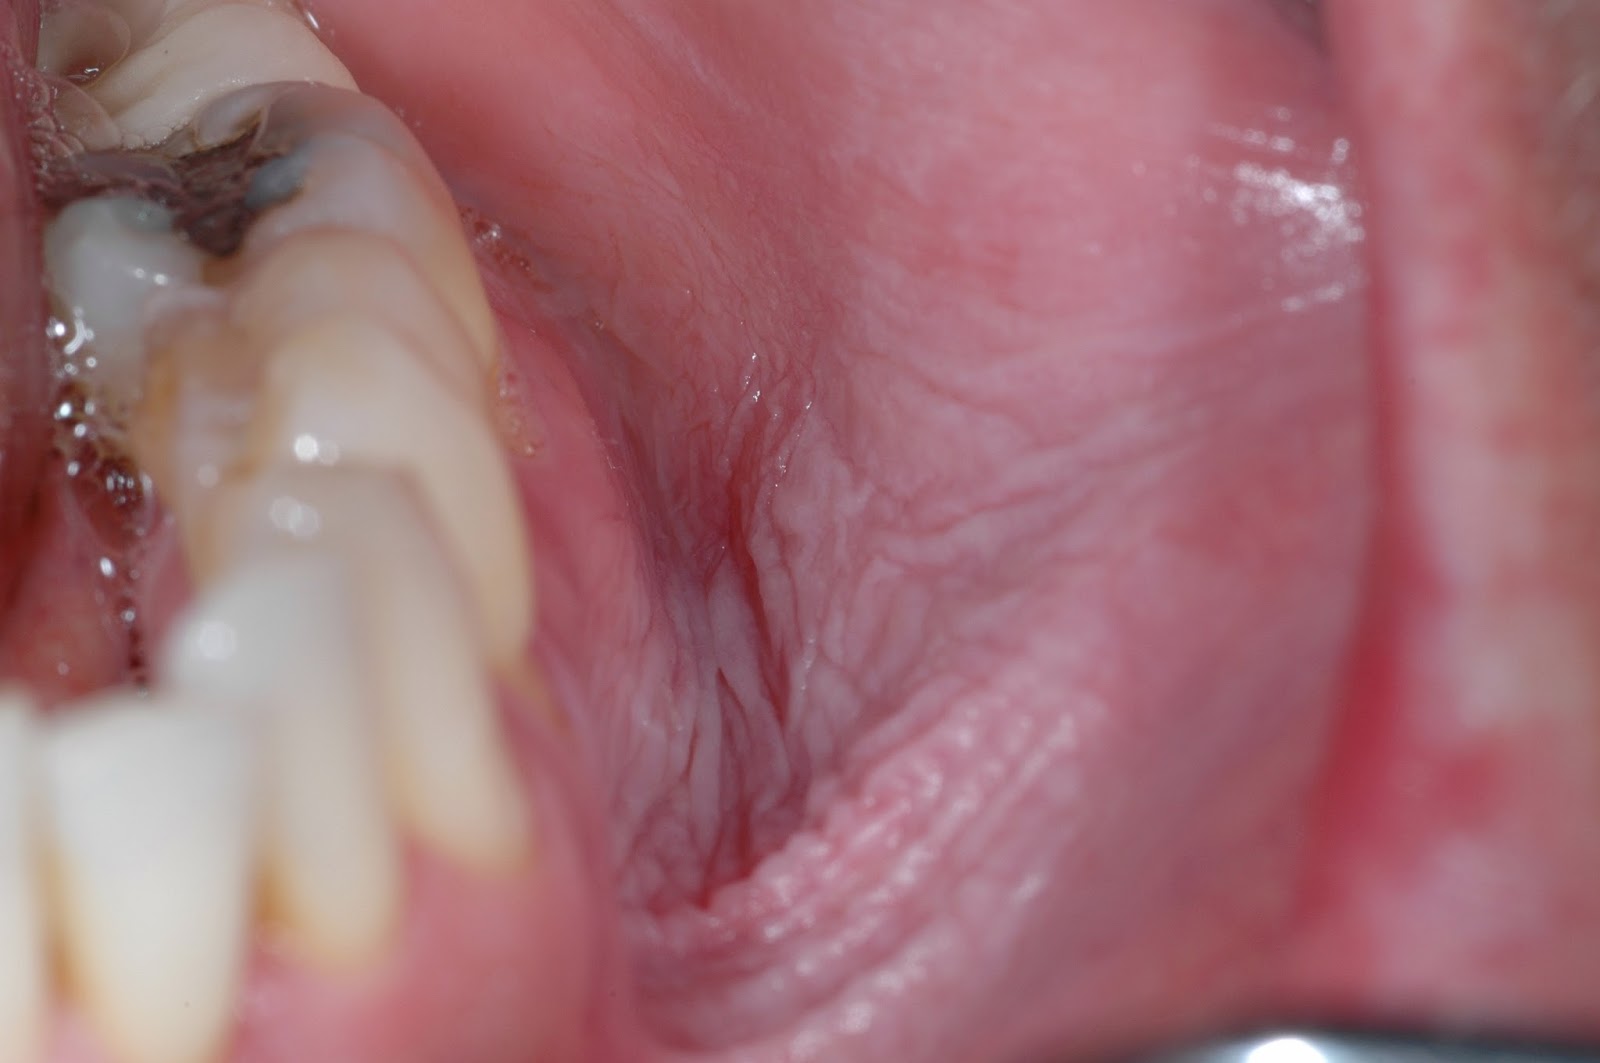

Smokeless Tobacco Gum Recession . In addition, it can also cause white or gray patches inside the. smokeless tobacco use as a risk factor for periodontal disease. traditional smokeless tobacco is still known to cause gum disease, dental decay, and tooth loss. severe attachment loss and gum recession was found among tobacco chewers. research has also linked smokeless tobacco use to receding gums. gum recession is when your gum tissue pulls away from your teeth, exposing the roots underneath. Kamath 1 supriya mishra 2 pradeep s. In severe cases, gum recession can lead to tooth loss if bacteria build up. It’s caused by a number. in general, localized attachment loss in the form of gingival recession occurs in 25 to 30% of. References [27, 28] suggest a.